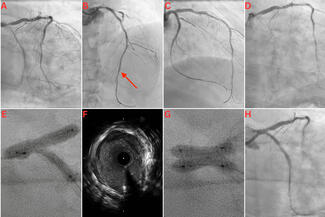

- Catch the Branch: The New Miracle Neo 3 Guidewire for Complex Bifurcation Rewiring

A 63-year-old man with a chronic total occlusion of the right coronary artery underwent successful retrograde recanalization. However, after stenting, plaque shift

caused a subocclusion of the ostial posterolateral branch, making side branch (SB) access difficult. When standard workhorse guidewires failed to re-engage the compromised SB ostium, operators turned to the Miracle Neo 3 guidewire, which successfully rewired the SB and reached the distal true lumen.